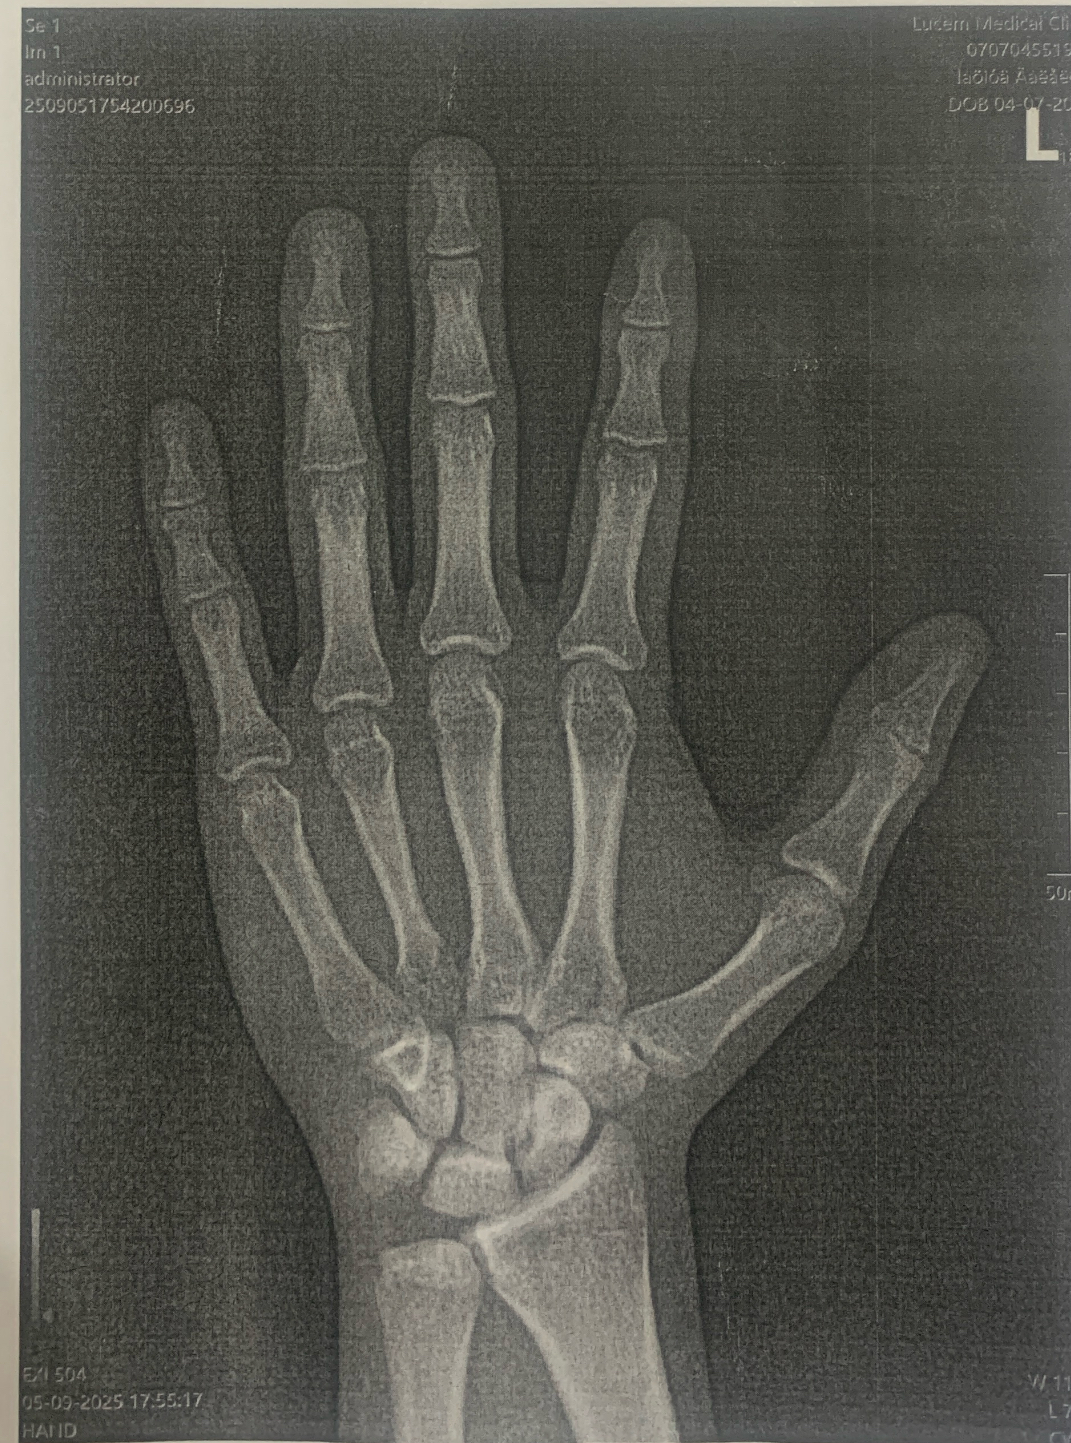

so i did the x ray of my wrist and doctors said i have bone age 12-13 and open plates. i'm 18 and 160cm if i blast hgh like 8+ ius ed will grow a few inches?

yes blast gh while u still can and show us the x-ray

idk if this is the right x-ray cuz other guys had it in other format not just printed on paper

hope for you this is not the actual x-ray otherwise you're coocked. This x-ray shows fully closed growth plates. Are you sure your doctor told your bone age was 13 and this is the right xray?